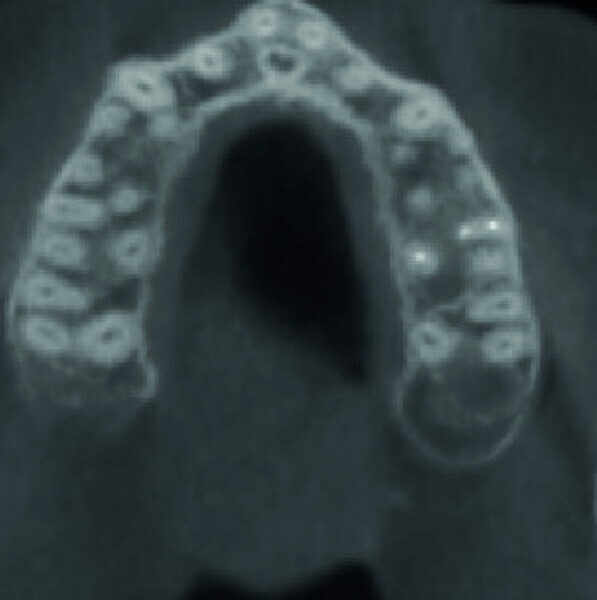

Maxillary sinus and root canal therapy complications